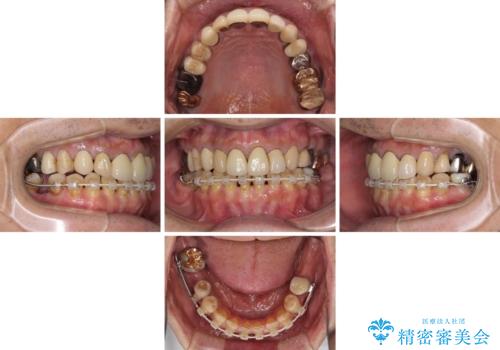

奥歯1歯分を動かすには時間がかかるため、矯正治療には思いの外時間がかかりました。

痛みのある奥歯は必要に応じて根管治療を行い、左下インプラントは角化歯肉の移植により清掃性を向上させ、気になっていた部分をしっかりと改善させることができました。